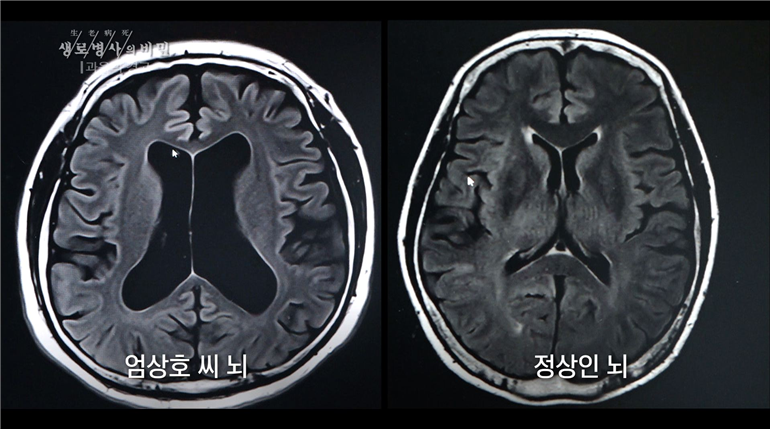

³ú ¼Õ»óÀÌ ´©ÀûµÇ¸é ¼úÀ» ¸¶½ÃÁö ¾ÊÀ» ¶§µµ ¼º°ÝÀÌ ³­ÆøÇϰųª ½Å°æÁúÀûÀ¸·Î º¯È­ÇÕ´Ï´Ù.

³ú°¡ ¹°¸®ÀûÀ¸·Î ÁÙ¾îµå´Â°Å¶ó ¤§¤§